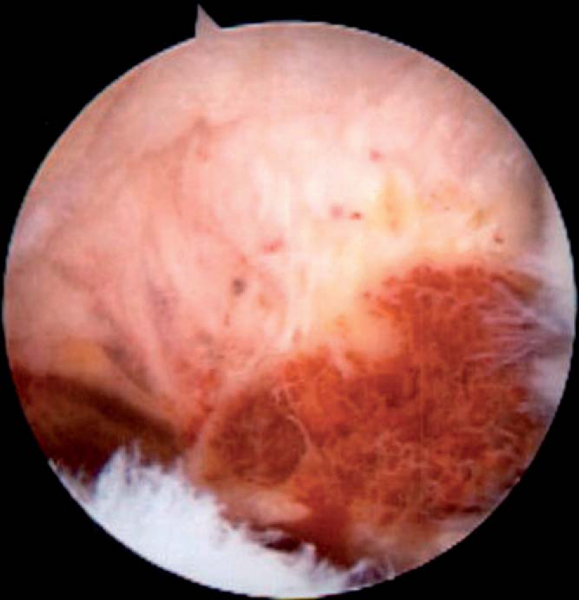

Pigmented villonodular synovitis has the characteristic appearance seen in other joints. However, it is not readily resected as it penetrates through the lining of the joint and expands outward into the surrounding structures (

Fig. 7-4

). Especially in inferior lesions, the synovial growth may envelope the axillary nerve, requiring its dissection either through open surgery or by arthroscopy.